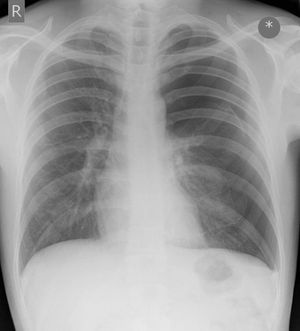

A 25 year old man presents to the emergency department with a two day history of dyspnoea. His pulse is 84/min, respiratory rate is 18/min and oxygen saturations are 97% on room air. The trachea is central on examination. You review his chest x-ray. What is the most likely clinical diagnosis? (please explain the cxr findings behind your choice) A. Left sided pneumothorax (no tension) B. Normal C. Left-sided tension pneumothorax D. Hyperexpansion secondary to severe asthma E. Right middle lobe pneumonia

Left sided pneumo. You can see the heart is shifted to the right. Even though the heart is shifted the pneumo is not hindering cardiac output as evidence by the patients clinical stability. Although vitals are stable treatment should be STAT chest tube placement as a patient like this could take a turn for the worse really quickly.

C Tension pneumothorax Ipsilateral increased intercostal spaces contralateral shift of the mediastinum depression of the hemidiaphragm.

Left sided simple pnuemothorax. CXR: Heart is shifted to right. Left lung parenchyma is collapsed. Clinically, young patient with mostly stable vitals and insidously developing symptoms (as compared to tension pneumothorax which is far more acute)